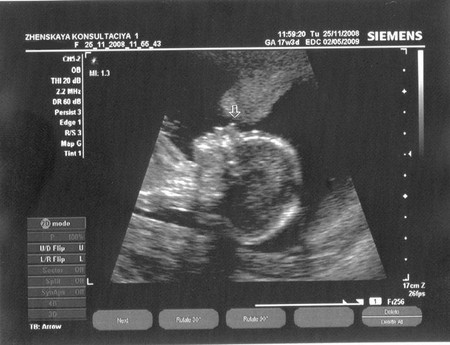

беременностьСегодня была на узи, сказали что у меня девочка :) Я честно говоря немного в смятении, так как почему-то была настроена на мальчика. Весь день привыкала к мысли что теперь надо думать о девочке :))

Вот такая вот у меня девица, уже похожа на меня носом :)) :